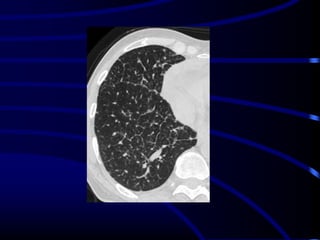

RBILD.

HRCT at the level of the upper

lobes exhibits an “ill-defined

centrilobular nodular pattern”

characterised by micronodules of

ground-glass opacity that are

diffusely distributed

characteristically in the centre of

the pulmonary lobules. In this case

the history of smoking favours the

diagnosis of respiratory

bronchiolitis interstitial lung disease